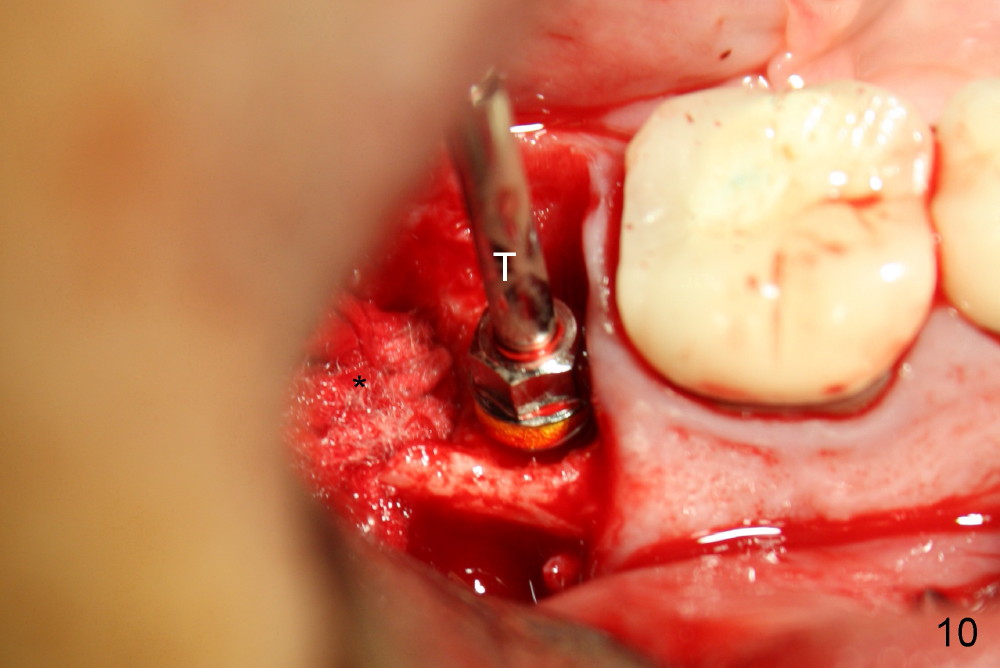

Then the

cyst is removed; hemorrhage is being controlled by gauze (Fig.10 *), while the

osteotomy is created in the mesial socket of #31 (4.5x17 mm tap in place: T

(Fig.10,11)). A 5x17 mm implant is placed with high torque (Fig.12 I).